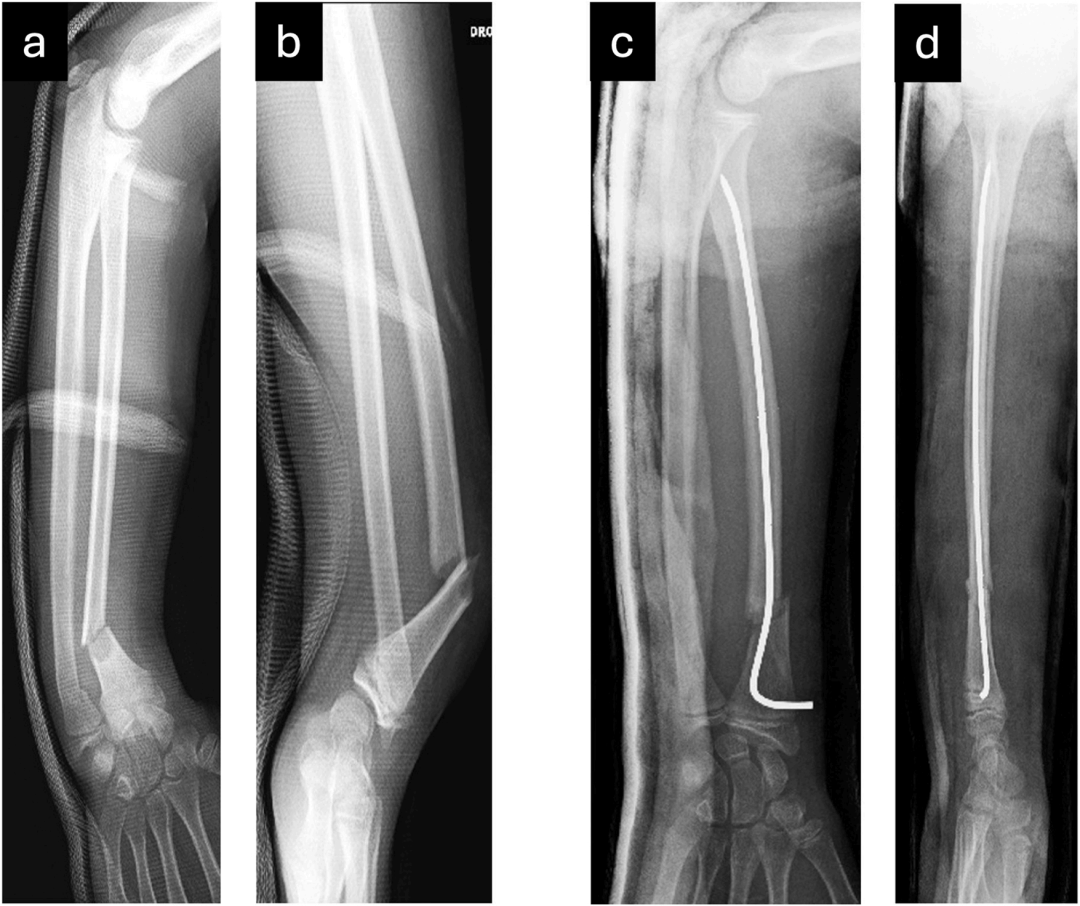

儿童桡骨骨折在复位后通常较为稳定,但极少数情况下,复位后仍存在不稳定,对于干骺端层面的骨折,可采用经骨折端穿针固定,该方法效果确切,对于骨干骨折,则可使用弹性稳定髓内钉(ESIN)。弹性稳定髓内钉具有诸多优包括微创操作、并发症发生率低以及固定稳定性佳等。 位于骨干与远端干骺端之间的中间区域,即远端干骺端-骨干连接部(DMDJ)的骨折,复位后稳定性较差。

这类骨折位置过于靠近端,不适用于经骨折端穿针固定,同时又过于靠远端,弹性髓内钉难以发挥充分的固定效果。因此术后常残留成角畸形。

还有学者将90°折弯改为S行,也增加了骨折的稳定性:

将S形结构进行如下折弯:使近端反折点支撑于桡侧骨皮质壁,S形的斜向部分穿过骨折线,远端反折点随即在尺侧支撑于骨皮质,如下图: